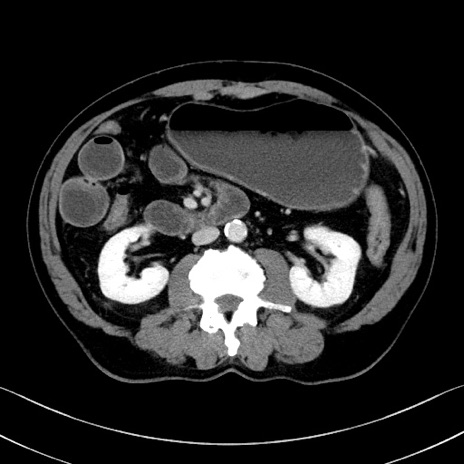

冠状断像

【症例】70歳代 男性

【主訴】腹部膨満、嘔吐

【現病歴】昨日より腹部膨満感出現。本日増悪し、仙痛出現。嘔吐あり、受診。

【既往歴】糖尿病、胆摘後

【身体所見】BP 149/80mmHg、HR 74/min、BT 35.9℃、腹部:膨満、軟、圧痛なし。腸雑音減弱あり。上腹部正中切開瘢痕あり。

【データ】WBC 13500、CRP 1.72